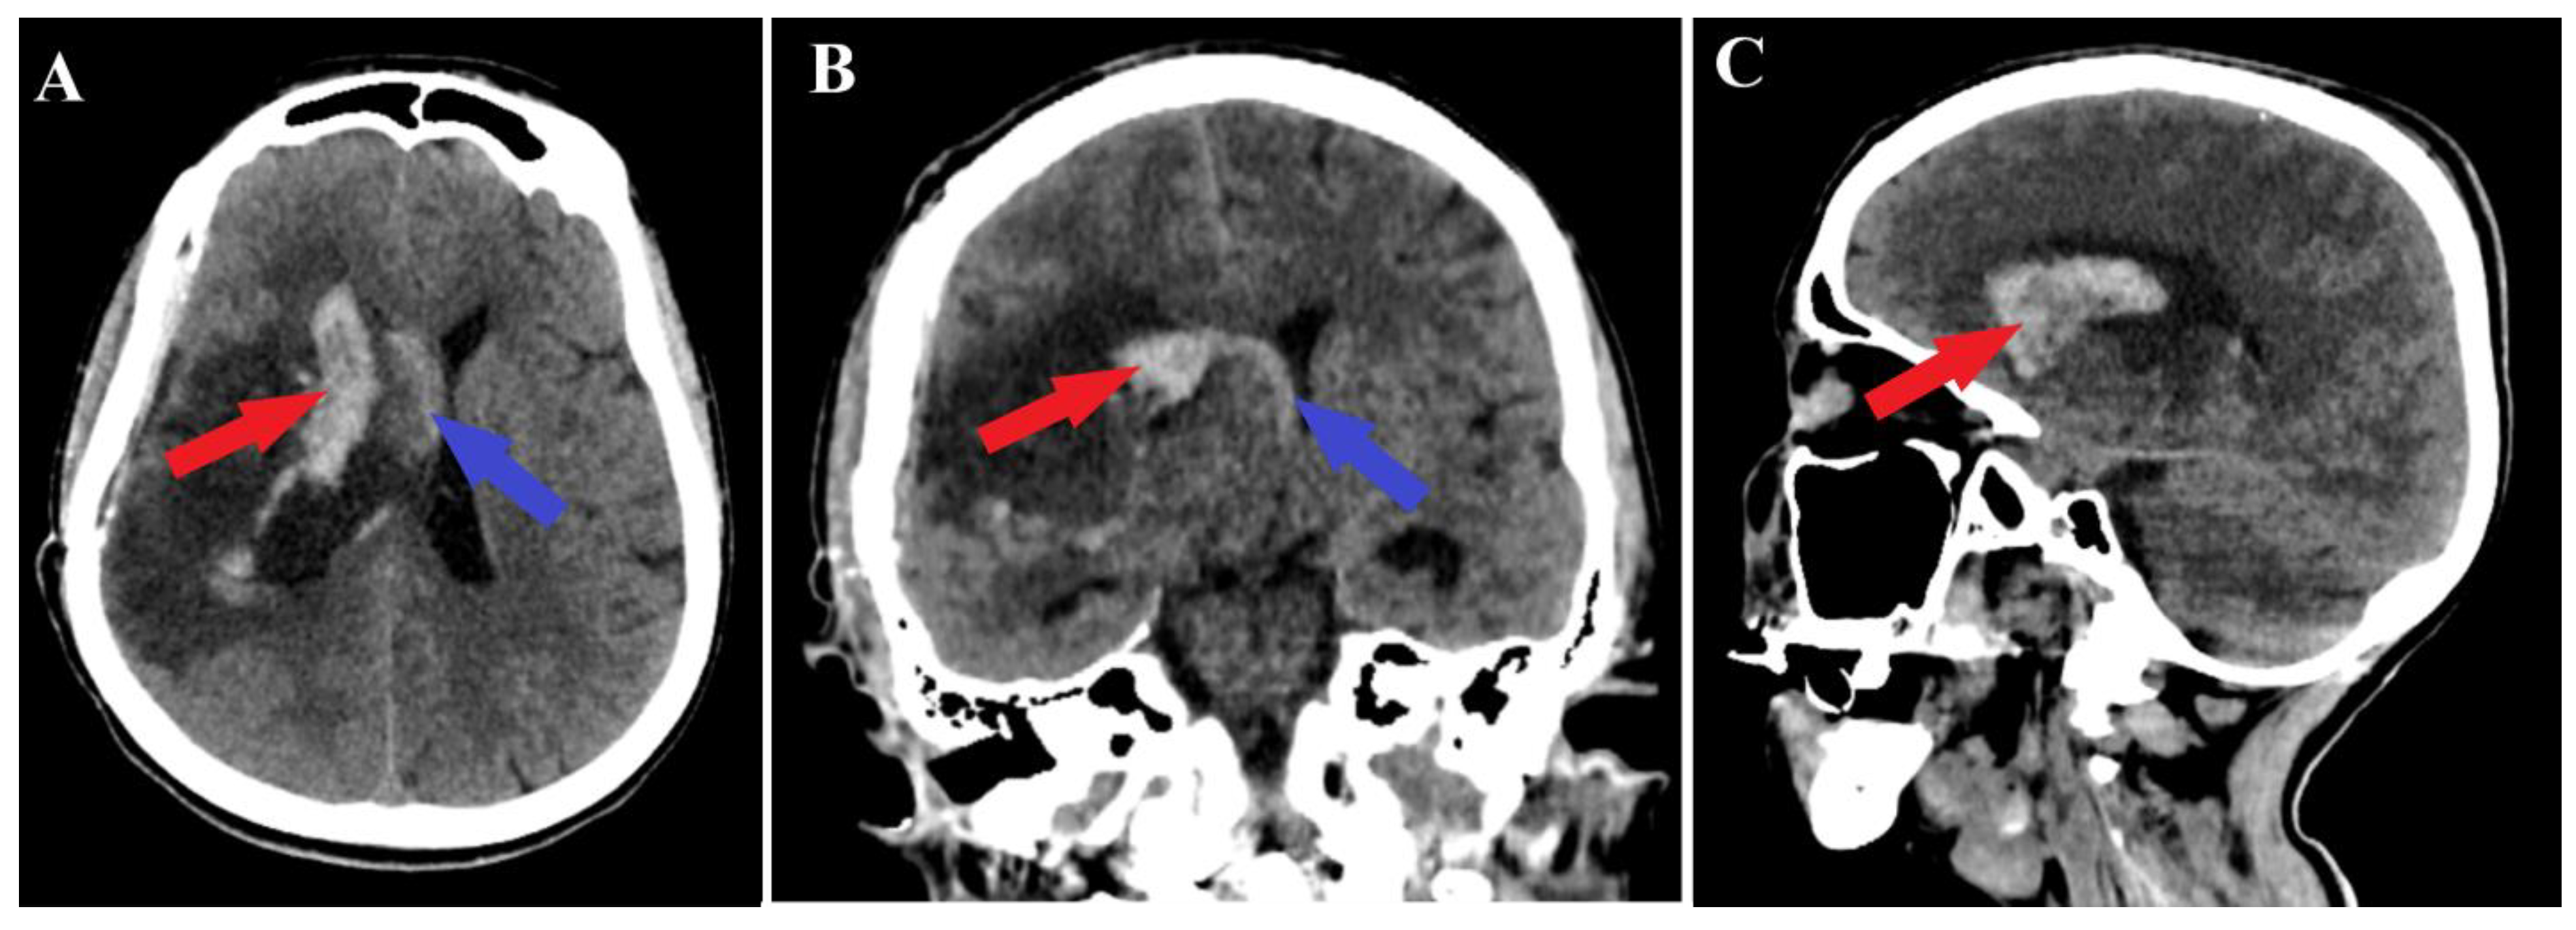

A 44-year-old patient was admitted to our clinic for sudden left hemiparesis MRC 1/5 occurring in the apparent health status 48 h prior to admission, followed by the deterioration of consciousness that become gradually worse, with the patient becoming comatose. She was admitted to our clinic with GCS = 7 points (eye response—2 points, verbal response—2 points, motor response—3 points), orotracheally intubated, and mechanically ventilated. Neurological examination on admission revealed a left hemiparesis, predominantly in the brachial region and comatose state. A brain non-contrast CT scan revealed a voluminous right fronto-temporal intraparenchymal hematoma with panventricular infiltration, significant mass effect on the right lateral ventricle, and 1.5 cm displacement of the midline. Otherwise, normal cerebroventricular CT appearance was seen (Figure 1). Angiography was performed through the selective injection of the internal carotid artery bilaterally, right external carotid artery, and left vertebral artery. Right temporal arteriovenous malformation with arterial afferents from the right anterior choroidal artery and right-sided middle cerebral artery was observed, Spetzler Martin grade III (Figure 2). A nidus of approximately 2/1 cm in size with several intranidal aneurysms was also observed (Figure 3). A single vein was draining into the right cavernous sinus, through an intermediate venous source.

Figure 1.

Preoperative CT scan. Axial section (A) highlights the intraparenchymal hematoma (red arrow); moreover, frontal (B) and sagittal (C) sections depict the massive hematoma with panventricular implication too (red arrows).